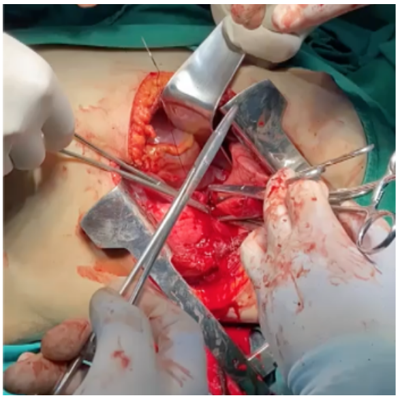

Vítima de colisão auto versus anteparo fixo, instável hemodinamicamente, recebeu os primeiros atendimentos em sala de trauma e foi encaminhada ao centro cirúrgico para realização do procedimento a seguir.

Considerando a imagem do intraoperatório, qual é o diagnóstico provável?